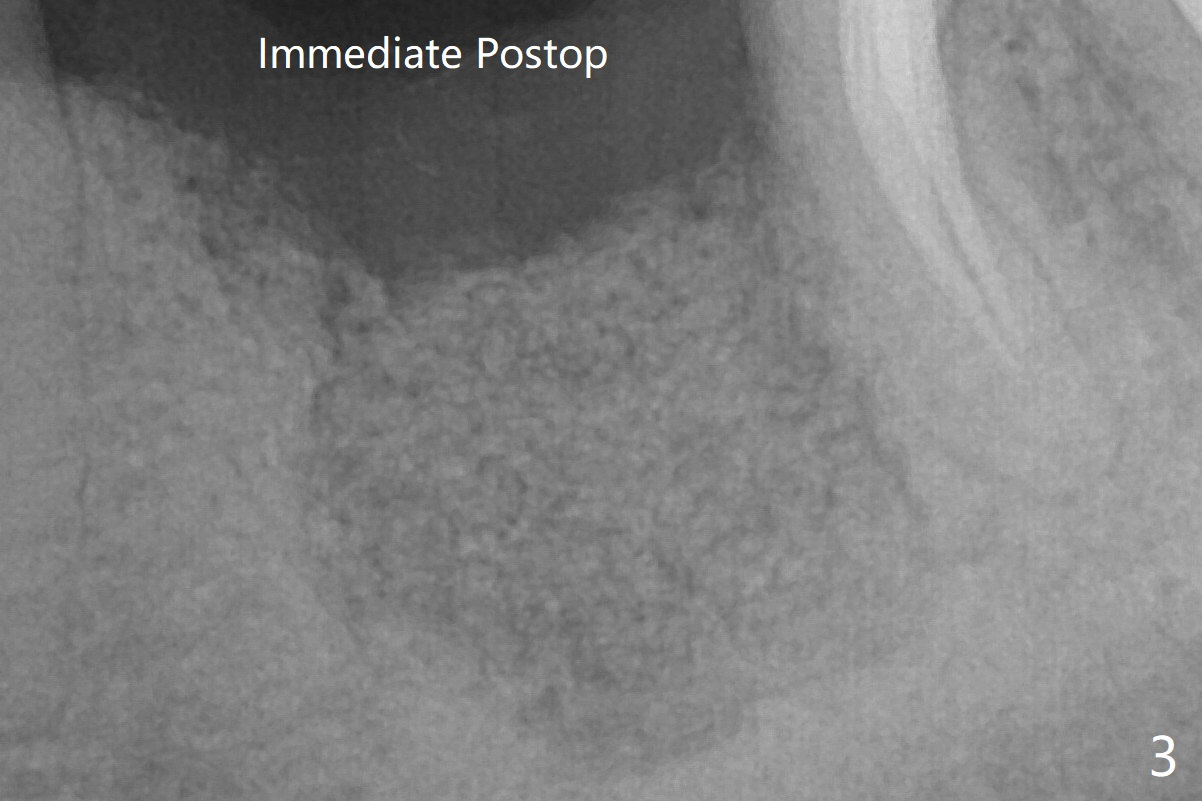

The low density bone in the middle of the socket is ignored (Fig.2 *, 3 S (soft)).  植骨后四个月,磨刀霍霍。Steven: 可能不够尤其远中,可能要再植骨,植入后没有初始稳定也不行。

病人来时,我也没有注意到植骨当中骨质密度低下,星号,它有可能当中血供不足导致。总之,没把它当一回事,应该再植骨。匆忙开始植牙